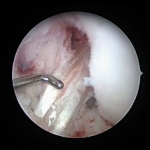

Plastia de LCA con tendones Isquiotibiales x4. Rodilla izda.